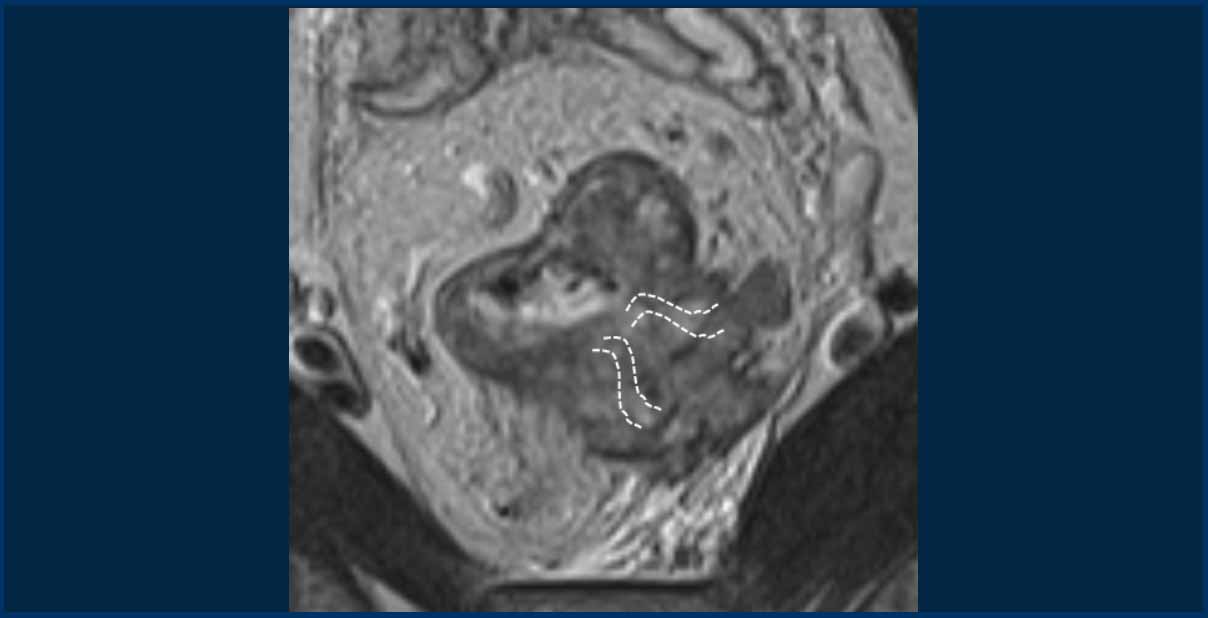

Images

The provided images demonstrate a signet-ring cell carcinoma with diffuse rectal wall thickening, the classic target appearance, and mesorectal fat infiltration.